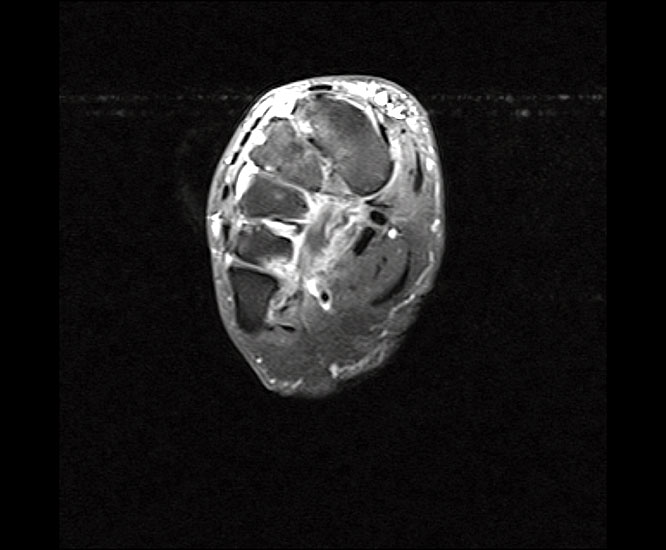

Querschnitt der Peronealsehnen in Höhe des Sprunggelenks.

Abbildung 2

Horizontal betrachtet liegt die Peroneus brevis Sehne der Fibulagleitfläche auf. Die Peroneus brevis Sehne hat einen halbmondförmigen Querschnitt. Auf dieser wiederum liegt die Peroneus longus Sehne.